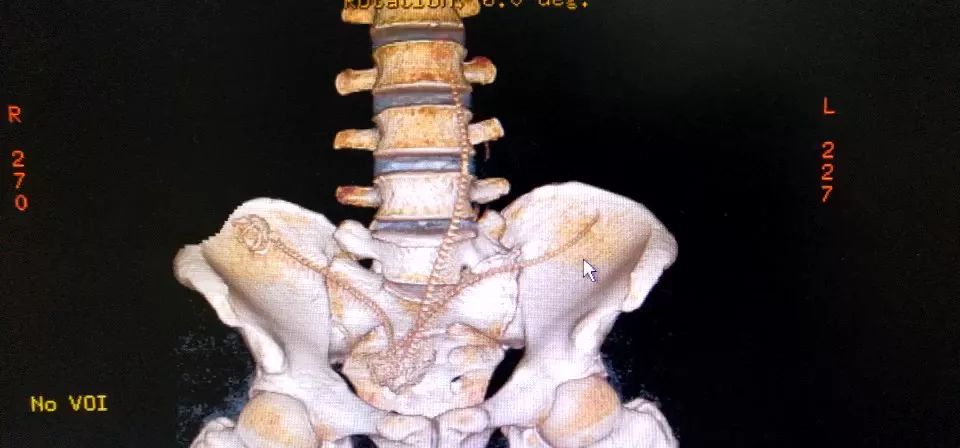

CT三维重建下三条泥鳅的骨骼清晰可见

占据整个下腹部和盆腔......